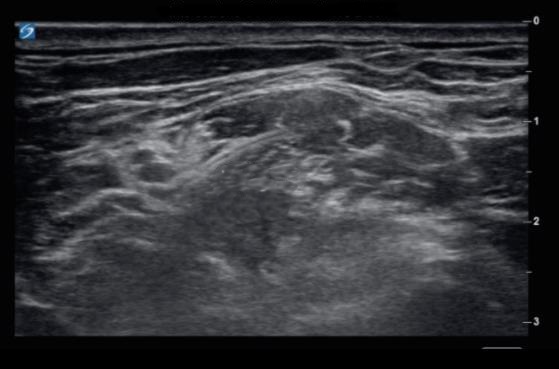

Amazon.co.jp: シンプルに打てる!外来での神経ブロック : 表。あっという間にうまくなる神経ブロック上達術|真興交易株式会社。肩の手術後の鎮痛のための横隔膜温存神経ブロック? パートI-NYSORA。斜角筋間神経ブロック - 連続カルーテル画像 | Sonosite。「シンプルに打てる!外来での神経ブロック」表 圭一定価: ¥ 7000#表圭一 #表_圭一 #本 #自然/医療・薬学・健康